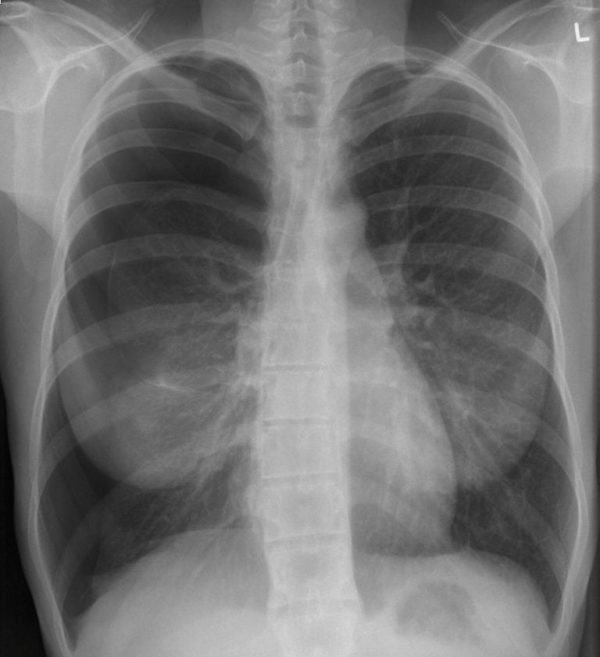

Descrivi e interpreta questa RX al torace

INTERPRETAZIONE DELLA RADIOGRAFIA AL TORACE

C’è un pneumotorace sul lato destro con collasso dei lobi superiore e inferiore. Il parenchima polmonare visualizzato sembra normale.

CORRELAZIONE CLINICA

Questo è un pneumotorace spontaneo primario di dimensioni moderate